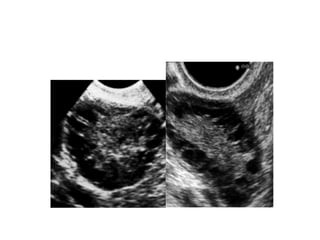

Le SOPK: Diagnostic Pas besoin de test dynamique/  Mesure de FSH, E2 (rech d’hypogonadisme hypogonadotrope devant spanio/aménorrhée), PRL? Testostérone Echo: nombre de follicules >12/ovaire, augmentation de volume  des ovaires(>10ml) Attention: première partie de cycle, opérateur dépendant.  Nouveau marqueur? AMH

Le SOPK: DiagnosticPas besoin de test dynamique/ Mesure de FSH, E2 (rech d’hypogonadisme hypogonadotrope devant spanio/aménorrhée), PRL? Testostérone Echo: nombre de follicules >12/ovaire, augmentation de volume des ovaires(>10ml) Attention: première partie de cycle, opérateur dépendant. Nouveau marqueur? AMH